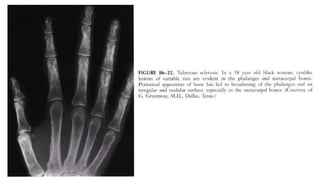

 Highly probable sarcoid arthritis includes the typical features of the

trabecular pattern, osteolysis, cyst formation, and punched-out lesions